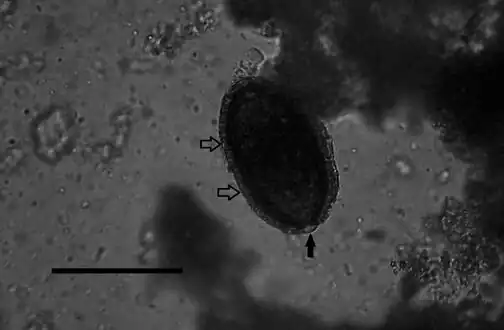

| One of the plates published with the original description of the species, showing the masses of eggs in the liver of the host (above) and free alive eggs (below). | |

Adult worms take the shape of a slender nematode, with the anterior part of the body narrow and the posterior part gradually swelling.[5] The females measure about 53–78mm x 0.11–0.20mm, but the males are approximately 24–37mm x 0.07–0.10mm.[5] The adult worms are rarely seen intact, as they mature and die in the parenchyma of the liver.[6] The adult females lay eggs that are about 48-66μm x 28-36μm.[5] The shell of the eggs is striated with shallow polar prominences at either end. Numerous mini-pores can be seen in the outer shell as well. Unembryonated eggs may be ingested by a carnivore, in which case they are harmless and pass out in the feces. Eggs will embryonate in the environment, where they require air and damp soil to become infective. Under optimal conditions this takes about 30 days. Larvae are juvenile versions of the adult worm.[1]

Diagnosis is made by finding eggs or adults of C. hepatica in liver tissue from biopsy or Necropsy samples.[1] The encapsulated eggs and adults may appear as white nodules which measure 2–3mm in diameter on the surface and interior of the liver at autopsy.[17] Key identification features of this parasite are a striated shell and shallow polar prominences of the egg and a narrowing at anterior end and gradual swelling at posterior end of the adult worm. Identification of C. hepatica eggs in the stool does not result from infection of the human host, but from ingestion by that host of livers from infected animals, the eggs will then pass out harmlessly in the feces.[1] Most cases have been determined after death because clinical symptoms resemble those of numerous liver disorders.[1]